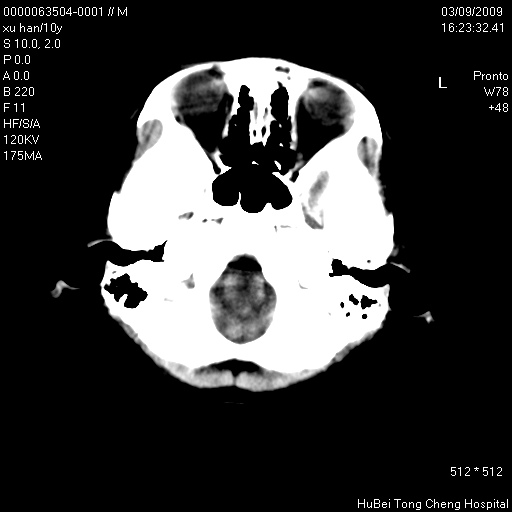

以下是引用道哥在2009-3-9 18:40:00的发言:[br]未见明显异常,必要时mr(dwi)成像。

以下是引用余辉在2009-3-10 11:01:00的发言:[br]考虑双侧海马急性缺氧性损伤